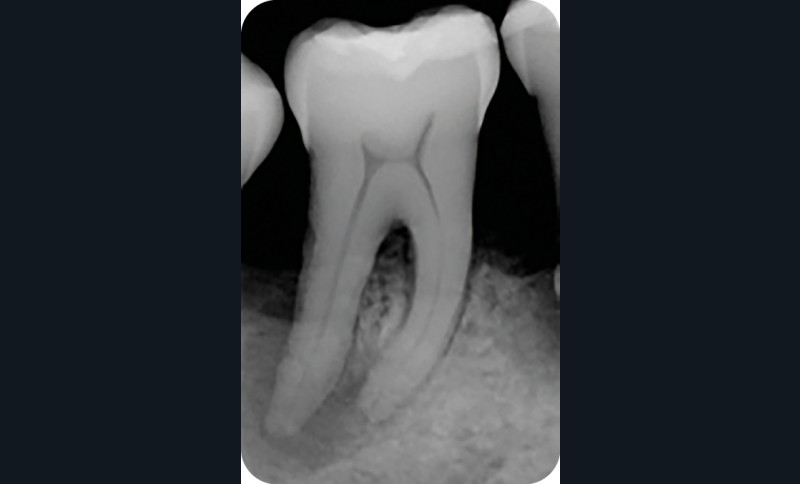

Radiographie préopératoire |

2. Exemple de prise en charge d’une lésion endo-parodontale sans atteinte de l’intégrité radiculaire, chez un patient atteint de parodontite, de grade 3 (poche parodontale profonde sur plus d’une surface dentaire). Le traitement endodontique est réalisé dans un premier temps. Après réévaluation à 6 mois, une contention a été placée et une thérapeutique parodontale complémentaire a pu être réalisée (surfaçage et mise en place de matériaux de comblement). La maintenance parodontale est effectuée régulièrement afin de maintenir le résultat obtenu.